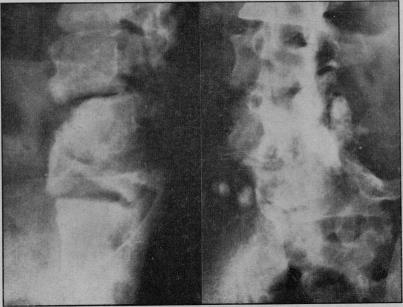

Tabetic spinal arthropathy.

Proc R Soc Med. 1953 Sep;46(9):747-52. doi: 10.1177/003591575304600908.